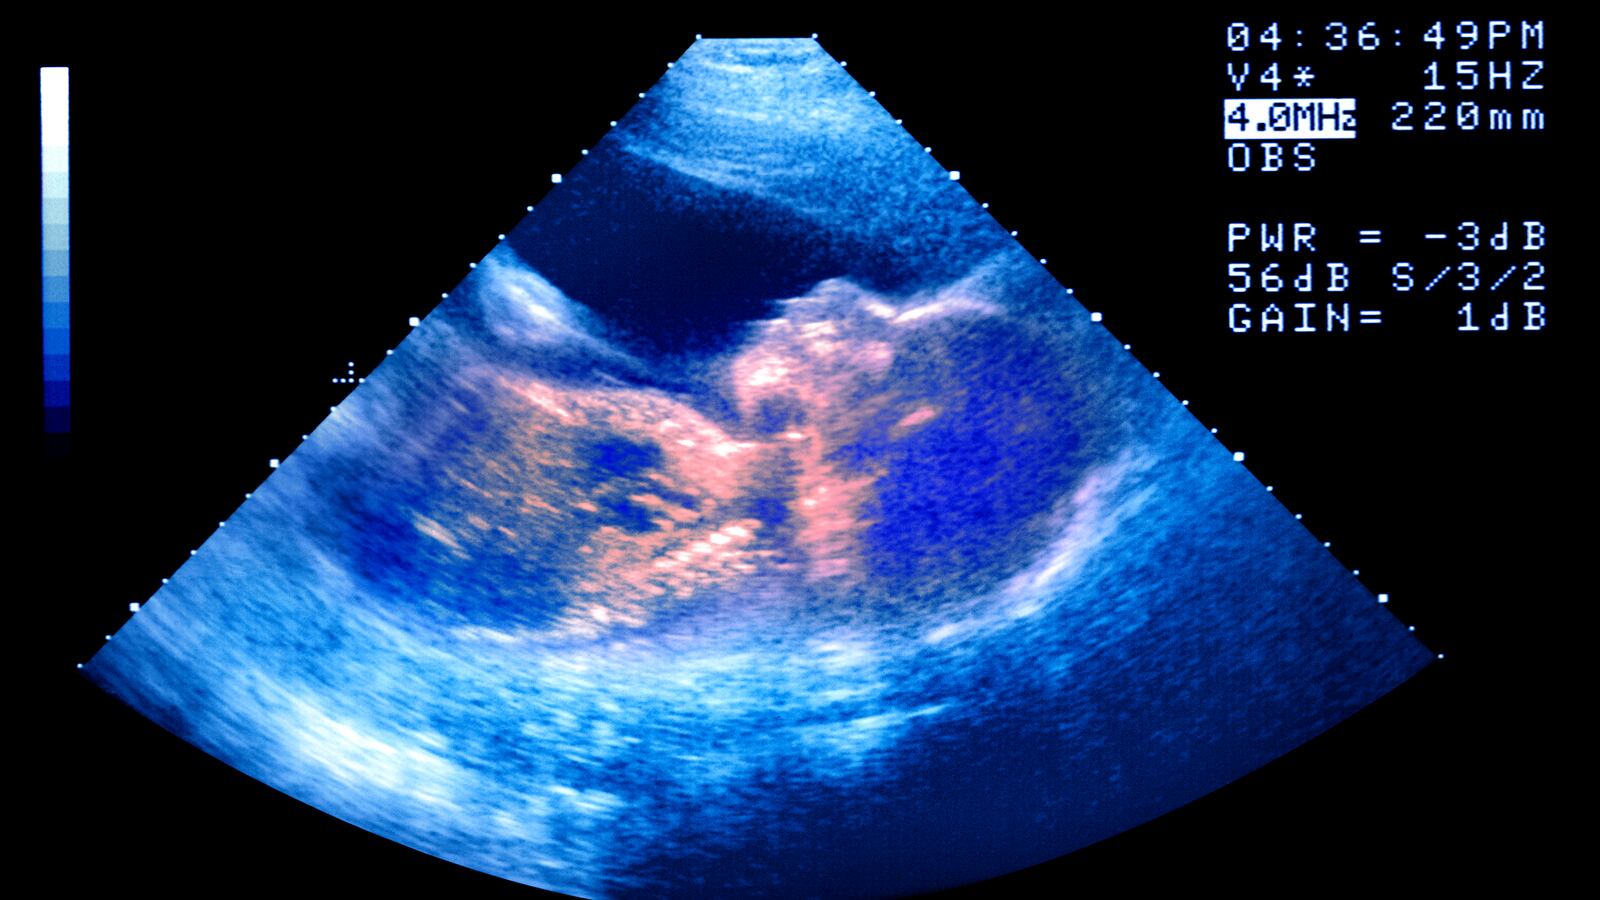

The pair had splashed out $100,000 for treatment at the CHA Fertility Clinic, leading to a successful pregnancy that they say they were told would bring them twin girls. But when the wife, identified in court papers only as A.P., gave birth in March 2019, she had twin boys.